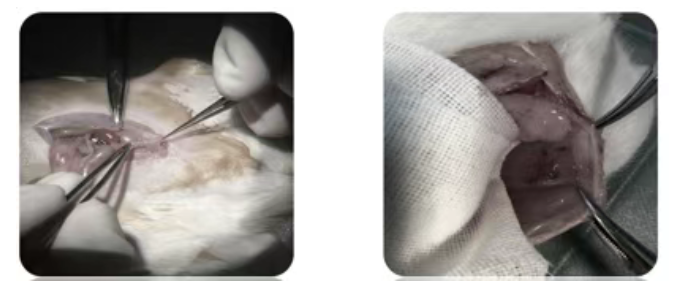

受体小鼠麻醉后,在腹壁做 1cm 切口,将子宫组织松散缝合于腹壁内表(避免过紧影响血供),且确保子宫内膜面朝腹壁,每侧缝合 1 块组织;

44a92673-d7b9-4da6-9041-b4fa3609813c.png

图2 受体小鼠子宫移植过程